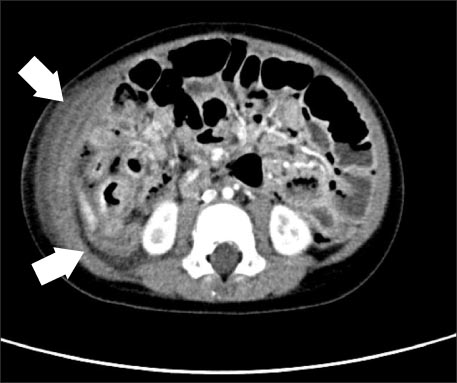

We considered this patient as bacterial enteritis and started symptomatic treatment. On the 3rd hospital day, the patient suddenly showed massive bloody stool. His vital signs were as follows: blood pressure, 95/70 mmHg; heart rate, 93 beats/min; respiratory rate, 21 breaths/min; and temperature, 39.5℃. Physical examination on abdomen showed rigidity, voluntary guarding and tenderness on palpation in the entire abdominal area. Bowel sounds were decreased. Laboratory data were as follows: sodium, 140 mEq/L; potassium, 3.3 mEq/L; chloride, 102 mEq/L; BUN/creatinine, 2.7/0.32 mg/dL; CRP, 118 mg/dL; and glucose, 93 mg/dL. The CBC was as follows: WBC, 15,420/µL; neutrophils, 69.4%; Hb/Hct, 8.9/26.6%; and platelets, 346,000/µL. Abdominal CT showed suspicious intraperitoneal and retroperitoneal abscess with air collection due to possible bowel perforation (Fig. 2).

Fig. 2

Abdominal CT shows suspicious intraperitoneal and retroperitoneal abscess with air collection due to suspicious bowel perforation (white arrows).

Fig. 2 Abdominal CT shows suspicious intraperitoneal and retroperitoneal abscess with air collection due to suspicious bowel perforation (white arrows).